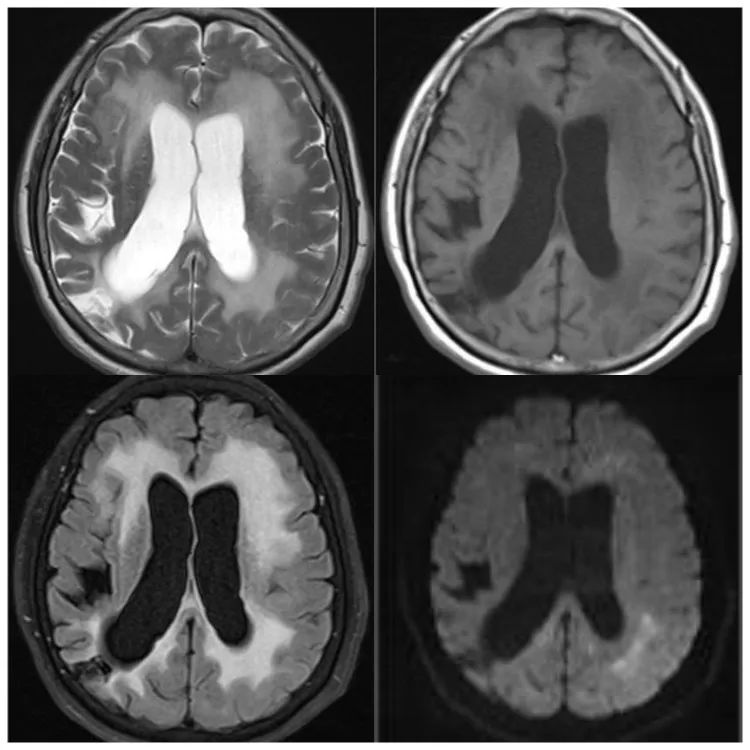

女,71 岁,一氧化碳中毒迟发性脑病,MR 表现双侧苍白球及胼胝体、侧脑室前角旁白质对称性异常信号,T1WI 呈低信号,T2WI、FLAIR 呈高信号,DWI 呈低信号。